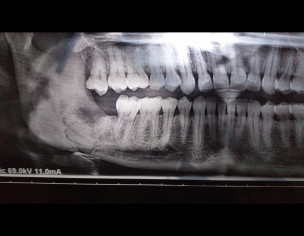

My sister had some roots under her wisdom tooth which we extracted through surgery but it was regrown. Then dr said its roots are so deep and reached end of jaw, so they did biopsy and it was non-malignant. Surgery took 4 hours and she was fine but her she had stitches twice ans infection is still there. Dr said may be we would need another surgery but when she visited him 3 days ago after taking antibiotics for a month he said bone has been developed and there is no need for surgery but we will need to do RTC for adjacent tooth as it is creating infection. I am attaching latest xray. Please dr explain if the bone is fine, and why infection is recurring.

She doesn’t need any further surgery or any root canal in adjacent teeth according to root canal

no need of another surgery, adjacent tooth seems fine no need for RCT

the socket looks fine a d so does the adjacent tooth. its an artefact that he might be confusing with caries or exposure on distal side of adjacent tooth.

just keep the oral hygiene maintained. healing will take place.

x-ray is not clear,I suspect jaw fracture at extraction site.please consult a nearby maxillofacial surgeon to rule out bone fracture.

There is jaw fracture at the site of extraction do go for opg and consult oral and maxillofacial surgeon. Adjacent tooth is fine main problem is at the extraction site.

the tooth adjacent to wisdom tooth is fine and doesn't require RCT. make sure to brush and clean ur mouth properly.

do visit a maxillofacial surgeon for a final assessment of the jaw bone healing and overall examination to rule out and possibility of infection or bone damage